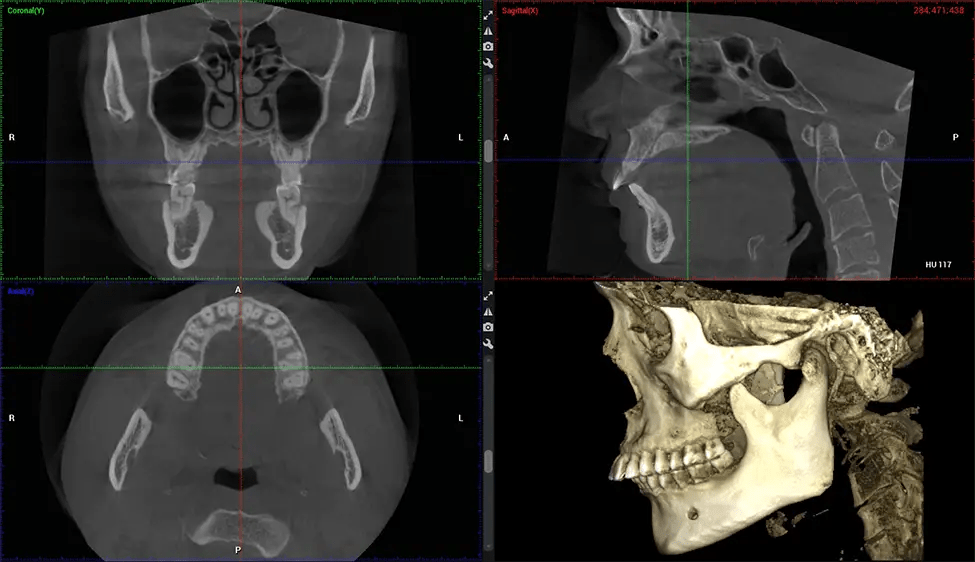

This 3D scan, called cone beam computed tomography, gives your dentist a more complete image of your oral anatomy and disease processes than a traditional X-ray. Unlike conventional X-rays, which capture a 2D image of your mouth from various angles, a 3D scan takes multiple digital X-rays for one image. It provides a complete view of your jaw, teeth, nerves, and soft tissues. This enhanced view allows dentists to detect minor issues not visible in traditional 2D scans, such as impacted wisdom teeth or bone fractures in the sinus cavity.

There are many benefits to using CBCT technology, especially compared to the traditional 2D X-ray format. One of the most significant advantages of CBCT scans is that they provide much more information than traditional X-rays. A scan lets your dentist see images from all angles of your jaw and mouth, including your sinuses, nasal cavity, cheekbones, and other surrounding areas. This added information helps your dentist craft a comprehensive treatment plan that addresses all aspects of your oral health.

After the scanning process, the captured X-ray images are processed by the CBCT software, which applies algorithms to reconstruct a detailed 3D image of the scanned area. The software compiles these individual X-ray images and creates a digital 3D representation of the patient’s anatomy. The reconstructed 3D CBCT image can be viewed and analyzed by the dentist or radiologist. This image can be manipulated, rotated, and zoomed in or out to examine specific structures and evaluate the patient’s condition.